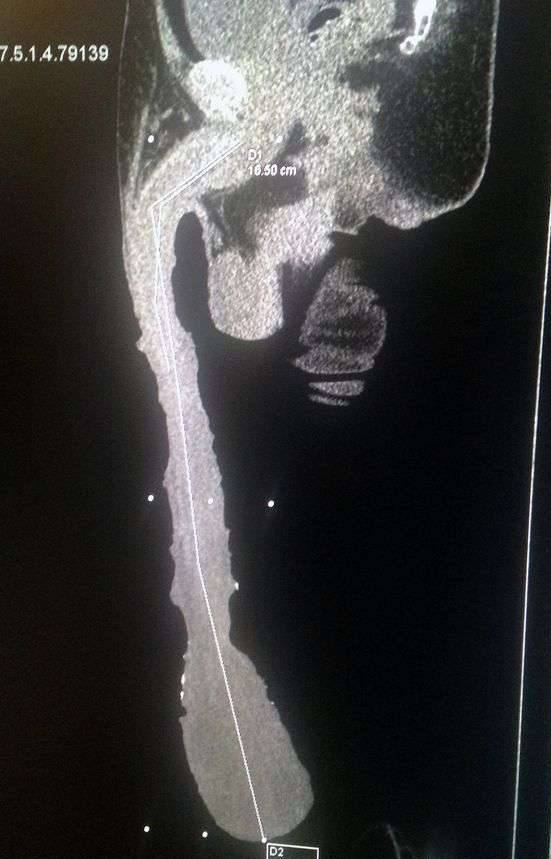

▼大多数人都会选择后者吧,但54岁墨西哥男子Roberto Esquivel Cabrera却毫不犹豫选择了前者。他的GG长度超乎寻常,未勃起前露出体外的部分就有48公分长,跟一匹成年公马差不多,但他的生活没有想像中那幺快乐。

▼之前他还申请过金氏纪录,但目前世界上还没有这样的项目,所以没成功。医生知道他的情况后,愿意为他提供资治疗,帮他把GG缩小到正常大小,Roberto却没有答应。他以自己非同寻常的GG自豪,也知道世界上没有比这更大的GG,这让他很开心,宁愿没有性生活,也不愿意通过手术变小。